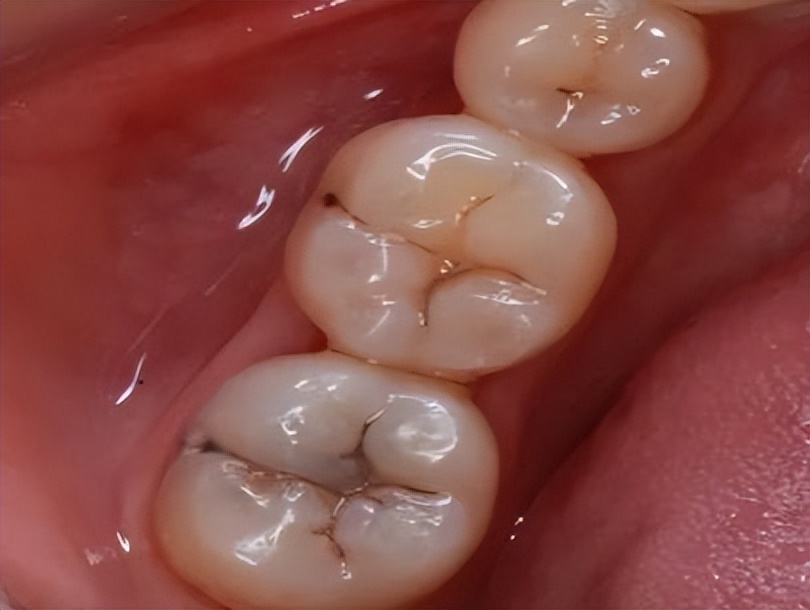

浅龋

病变局限牙齿浅层。一般无自觉症状,仅在检查时发现牙齿局部颜色改变。

这个阶段吃苹果基本没有感觉,口感嘎嘣脆,香甜依旧。